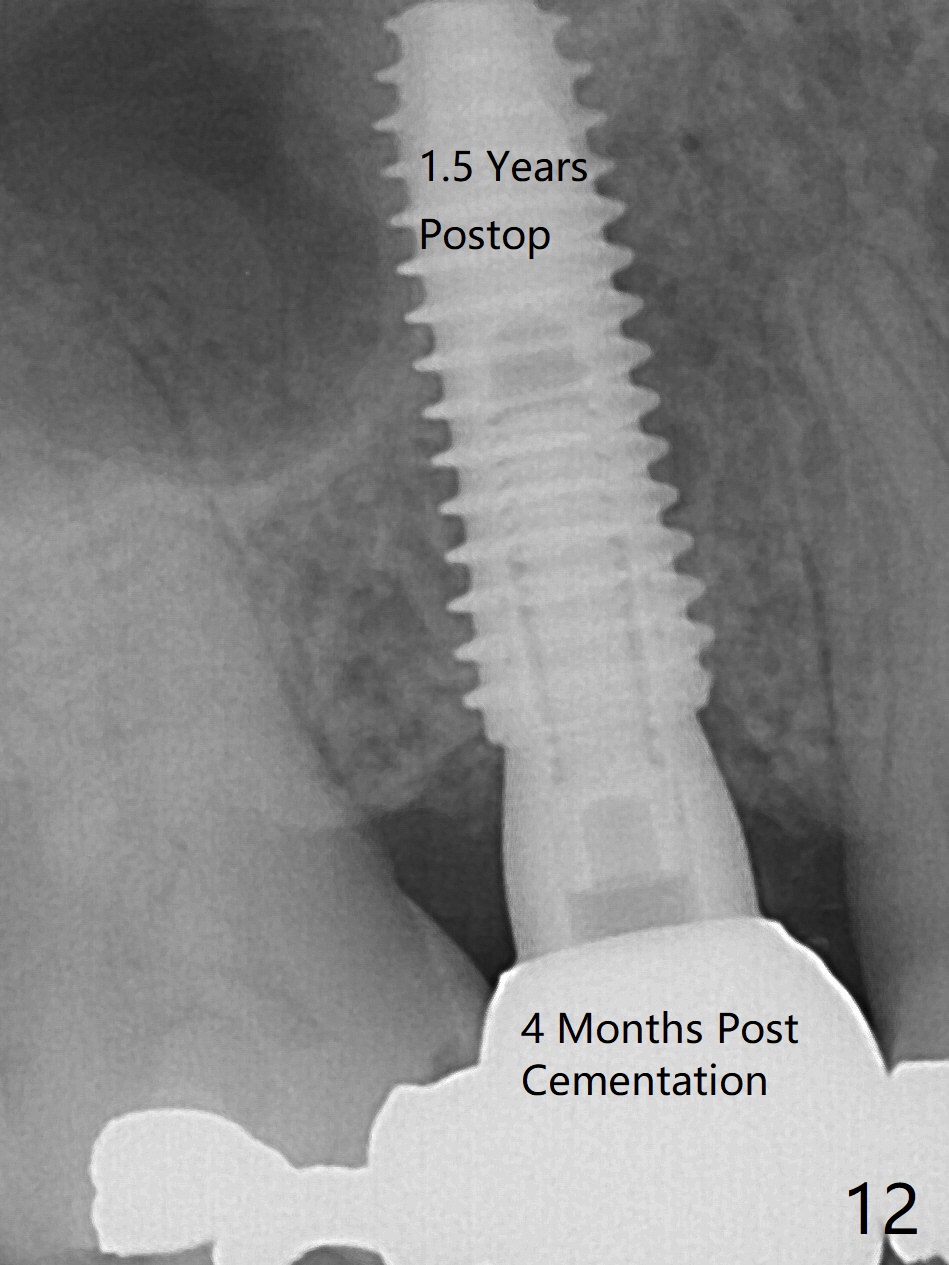

The 48-year-old man agrees to extract the tooth #4 with buccal and palatal fistulae (Fig.1,2 >) and large PARL (Fig.3 *) because of purulent discharge. The large post (Fig.3 P) is most likely associated with a longitudinal fracture. The latter is not noted until postop (Fig.4 <). Intraop finding is large amount of granulation tissue removed from the mesial apical region (Fig.3,5 *). With 10.5 mm offset, Sinus Approach Drill (19 mm) is estimated too short for sinus lift after 3x8.5 mm drill. Without careful repeated check, 2.2x10 and 2.2x11.5 mm drills are used. The sinus floor is perforated, but the membrane seems to be intact. The perforation is too small to insert PRF, but alright for allograft. Then nose blowing test shows that the sinus membrane is perforated, which seems to be repaired after placement of 2 pieces of PRF membrane, followed by another round of allograft (Fig.5 G), which is lifted by a 4x10 mm IS dummy implant. Before placement of a 4.5x11.5 mm final UF implant, allograft is placed in the 3 defective bony areas mentioned above, including the apical mesial one (Fig.6 *). But the final UF implant seems too short with non-satisfactory torque. The latter appears to be solved with the increased length of the implant (Fig.7). The gingiva around the provisional (P) is healthy without fistulae buccal (Fig.8) or palatal 17 days postop (Fig.9). A new abutment with 1 mm longer cuff is seated completely 5.5 months postop (Fig.10 < (no gap), as compared to Fig.7). The lower portion of the mesial defect seems to have been repaired (Fig.11 arrow, as compared to Fig.7). The bone in the sinus seems stable 1.5 years postop (Fig.12). There is no crestal bone loss 4 months post cementation (Fig.13). Return to Upper Premolar Immediate Implant, Trajectory II Xin Wei, DDS, PhD, MS 1st edition 09/27/2019, last revision 04/12/2021